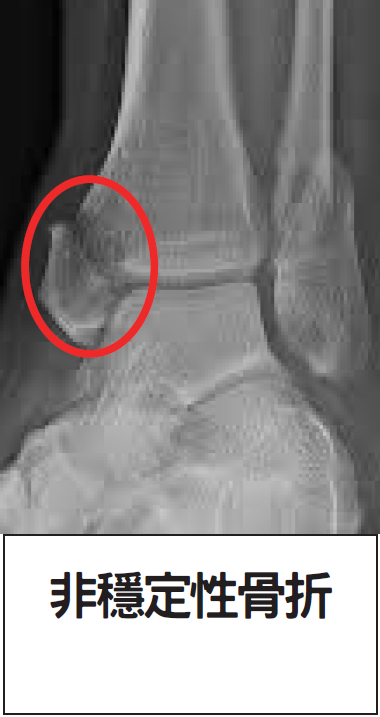

非穩定性骨折: 若骨頭出現裂縫分離或位置移位(如下圖),則屬非穩定性骨折。